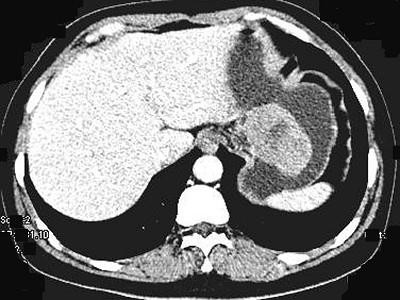

问题 女,51岁,上腹部隐痛不适,CT检查如图,可能的诊断是 ( )

选项 A、胃溃疡 B、胃间质瘤 C、胃息肉 D、胃腺瘤 E、胃癌

答案 B